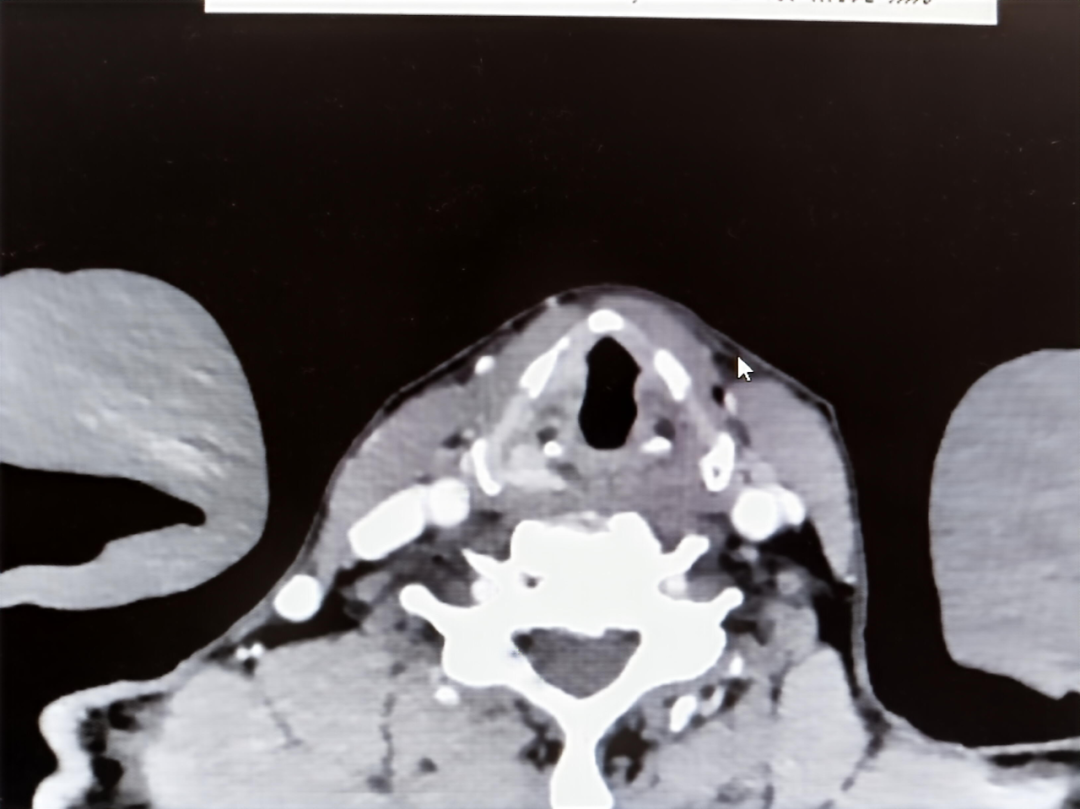

△颈部增强CT示右侧劈裂较对侧略增厚

在北大人民青岛医院,电子喉镜清晰显示李先生右侧声带上长出了一个表面不光滑的新生物,而这正是早期喉癌的迹象!